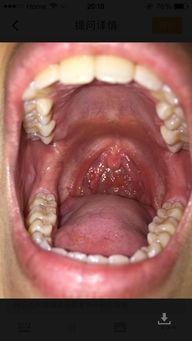

喉咙疼是一种非常痛苦的经历。灵宝告诉我们,那种感觉就像是有无数根针在喉咙里扎一样,让人难以忍受。她甚至无法正常说话,吃饭都成了问题。这种痛苦让她深刻体会到了健康的重要性。